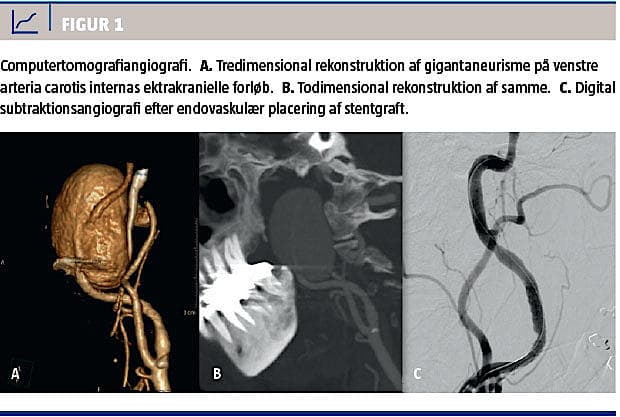

En magnetisk resonans (MR)-skanning ti dage efter bilateral tonsillektomi viste PA på venstre carotis interna, hvorefter patienten blev overflyttet til et tertiært sygehus. En computertomografiangiografi (CTA) viste et ekstrakranialt gigantaneurisme på 30 × 28 × 42 mm på venstre carotis interna under basis cranii (Figur 1). Aneurismet var ikke tilgængeligt for åben kirurgi, hvorfor der blev foretaget endovaskulær behandling.

Patienten blev forbehandlet med 75 mg clopidogrel og 150 mg acetylsalicylsyre dagligt i fire dage inden proceduren. Da blodpladehæmningen var utilstrækkelig ved behandling med clopidogrel, blev der skiftet til 10 mg prasugrel. Der blev med patienten i generel anæstesi placeret en stentgraft (Aneugraft 4 × 27 mm ITGI medical) ud for aneurismet, hvorefter stenten dilateredes med ballon. Ved afslutning af behandlingen sås der total lukning af aneurismet og en åbentstående carotis interna (Figur 1). Umiddelbart postoperativt forsvandt patientens globulusfornemmelse.